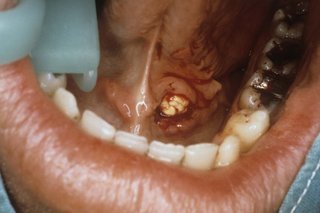

The inside of a person's mouth showing their lower teeth and part of their bottom lip. There is a small, white salivary gland stone under their tongue.

They vary in size, but most are as big as a pea.